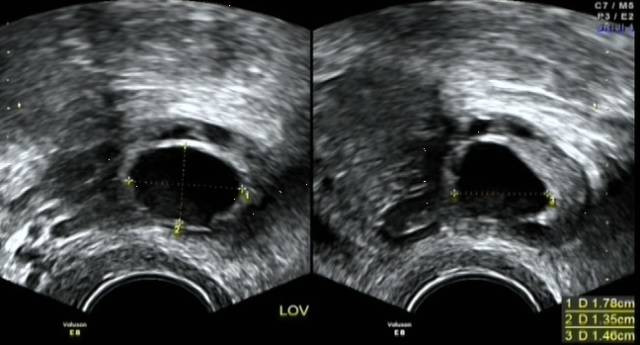

而B超是目前较为准确的一种排卵监测方式,它不仅可以测出两侧卵巢中是否有优势卵泡,同时还能测出优势卵泡的大小、子宫内膜的厚度等。

B超监测,通过动态观察卵泡超声图像的变化,准确地预测排卵,进而指导同房时间,大大增加受孕的几率。